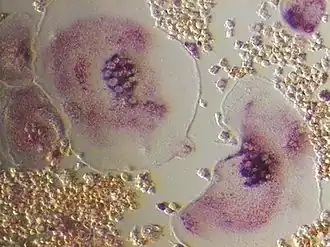

Imagen tomada con un microscopio óptico en la que se observan osteoclastos positivos a la fosfatasa ácida tartrato resistente. | ||

Los osteoclastos se caracterizan por poseer una porción de su membrana "arrugada", en forma de cepillo, rodeada de un citoplasma libre de orgánulos llamada "zona clara", con la que se adhiere a la superficie del hueso mediante integrinas, unos receptores especializados del hueso. El proceso de resorción se inicia cuando el aparato de MRD de las células excreta lisosomas con enzimas capaces de producir un microambiente ácido por debajo de la membrana arrugada como consecuencia del transporte de protones mediante la bomba de protones ATP-dependiente, el intercambio Na+/H+ y la anhidrasa carbónica. Las enzimas lisosomales de los osteoclastos implicadas en este proceso son cistein-proteasas como la catepsina y sobre todo, la fosfatasa ácida tartrato-resistente (esta última se utiliza como marcador del fenotipo osteoclástico). Las enzimas lisosomales solo son liberadas en la zona clara en las proximidades del borde arrugado produciéndose en esta área las reacciones de degradación de la matriz que deben producirse antes de que el medio ácido disuelva las sales minerales del hueso.